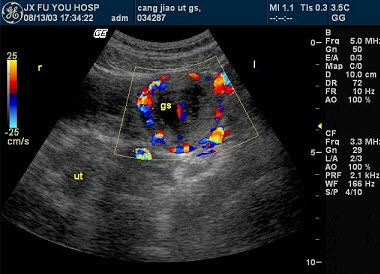

86、单项选择题

该病例最有可能诊断()

A.肺动脉内径增宽

B.动脉导管未闭

C.肺动脉瓣狭窄

D.肺动脉瓣关闭不全

E.右室流出道狭窄